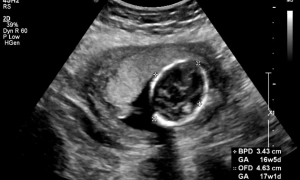

Higher nuchal translucency in ultrasound tied to increased chromosomal anomalies risk: JAMA

A recent study from Ontario, Canada, unveiled a strong link between…